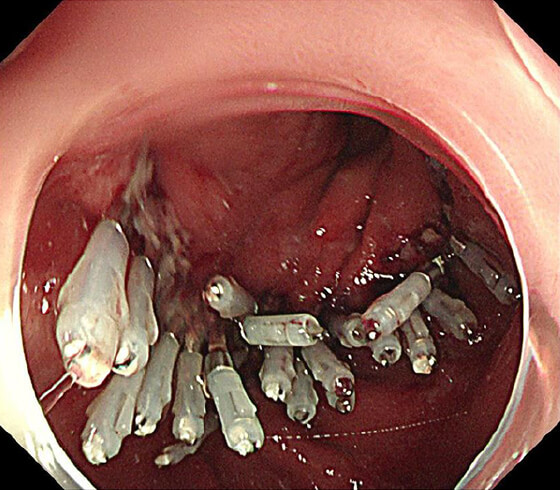

PDT

PDT 5ヶ月後